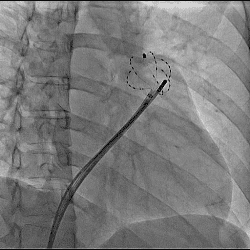

経皮的心筋燃焼灼術(カテーテル・アブレーション)の一例

-

- 【1】多発性心室性期外収縮に対しての一例

- 【2】発作性心房粗動に対しての一例